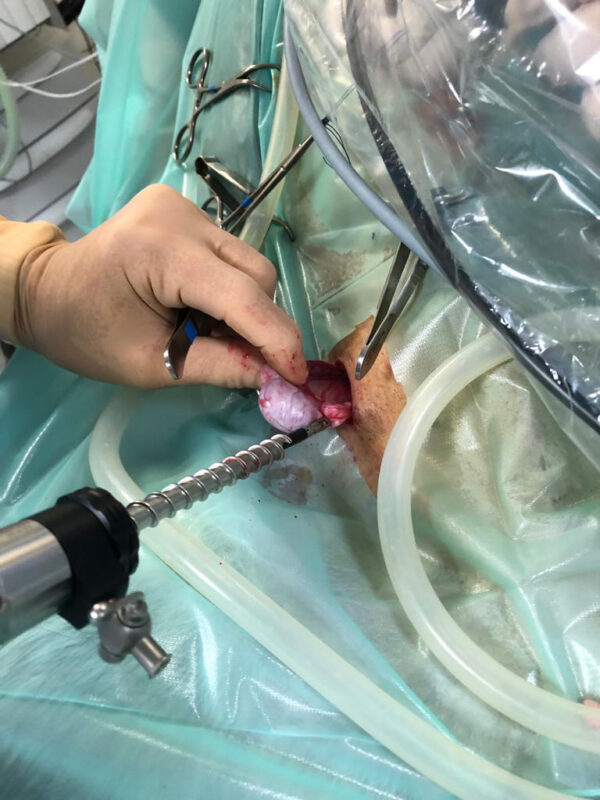

Denk hierbij bijvoorbeeld aan het verwijderen van een binnenbal die in de buik ligt (cryptorche testikel), waarbij er laparoscopisch geassisteerd wordt. Door middel van een echo is er eerst gekeken waar de testikel ligt.

Op de operatietafel kunnen we vervolgens met behulp van de scoop de cryptorche testikel nauwkeurig lokaliseren en bepalen waar de bloedvaten zitten, die we niet willen raken. Vervolgens kan dan zeer gericht een 2e trocar (dit is een canule van bijvoorbeeld 5 mm breed, waardoor je vervolgens met een tang de buik in kunt) geplaatst worden om de testikel tegen de buikwand te halen en te kunnen verwijderen. Al met al heb je dan 2 veel kleinere gaatjes in vergelijking met een echte buikoperatie.